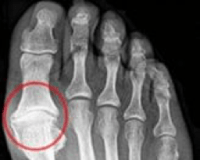

• Рентгенография стопы. Зазор соединения уменьшен. Контуры суставов конечностей неровные, есть остеофиты. В костной ткани видны очаги разрежения, вызванные образованием кист.